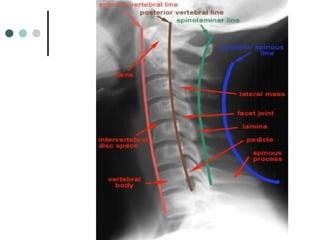

C-spine Film Interpretation

1. Count Vertebrae

-C1 through C7

-If T1 not seen do Swimmer’s view

2. Assess Curvature

3. Assess Vertebral Alignment (4 lines)

-ant vertebral line

-post vertebral line

-spinolaminal line

-post spinal line

4. Assess Bony Integrity

5. Assess Intervertebral Disk Spaces

6. Soft Tissues

C-spine Film Interpretation 1.Count Vertebrae -C1 through C7 -If T1 not seen do Swimmer’s view 2. Assess Curvature 3. Assess Vertebral Alignment (4 lines) -ant vertebral line -post vertebral line -spinolaminal line -post spinal line

C-spine Film Interpretation 4.Assess Bony Integrity 5. Assess Intervertebral Disk Spaces 6. Soft Tissues